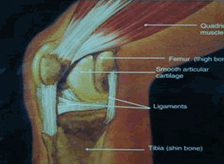

ข้อเข่า

เป็นข้อรับน้ำหนักที่ใหญ่ที่สุดของร่างกาย ข้อเข่าที่ปกติและมีสภาพที่ดี ต้องมีคุณสมบัติ คือ เป็นข้อที่เคลื่อน ไหวได้ดี ไม่ทำให้ปวด และมีความมั่นคงในขณะใช้งาน

รูปภาพ ภาพวาดแสดงข้อเข่าปกติ